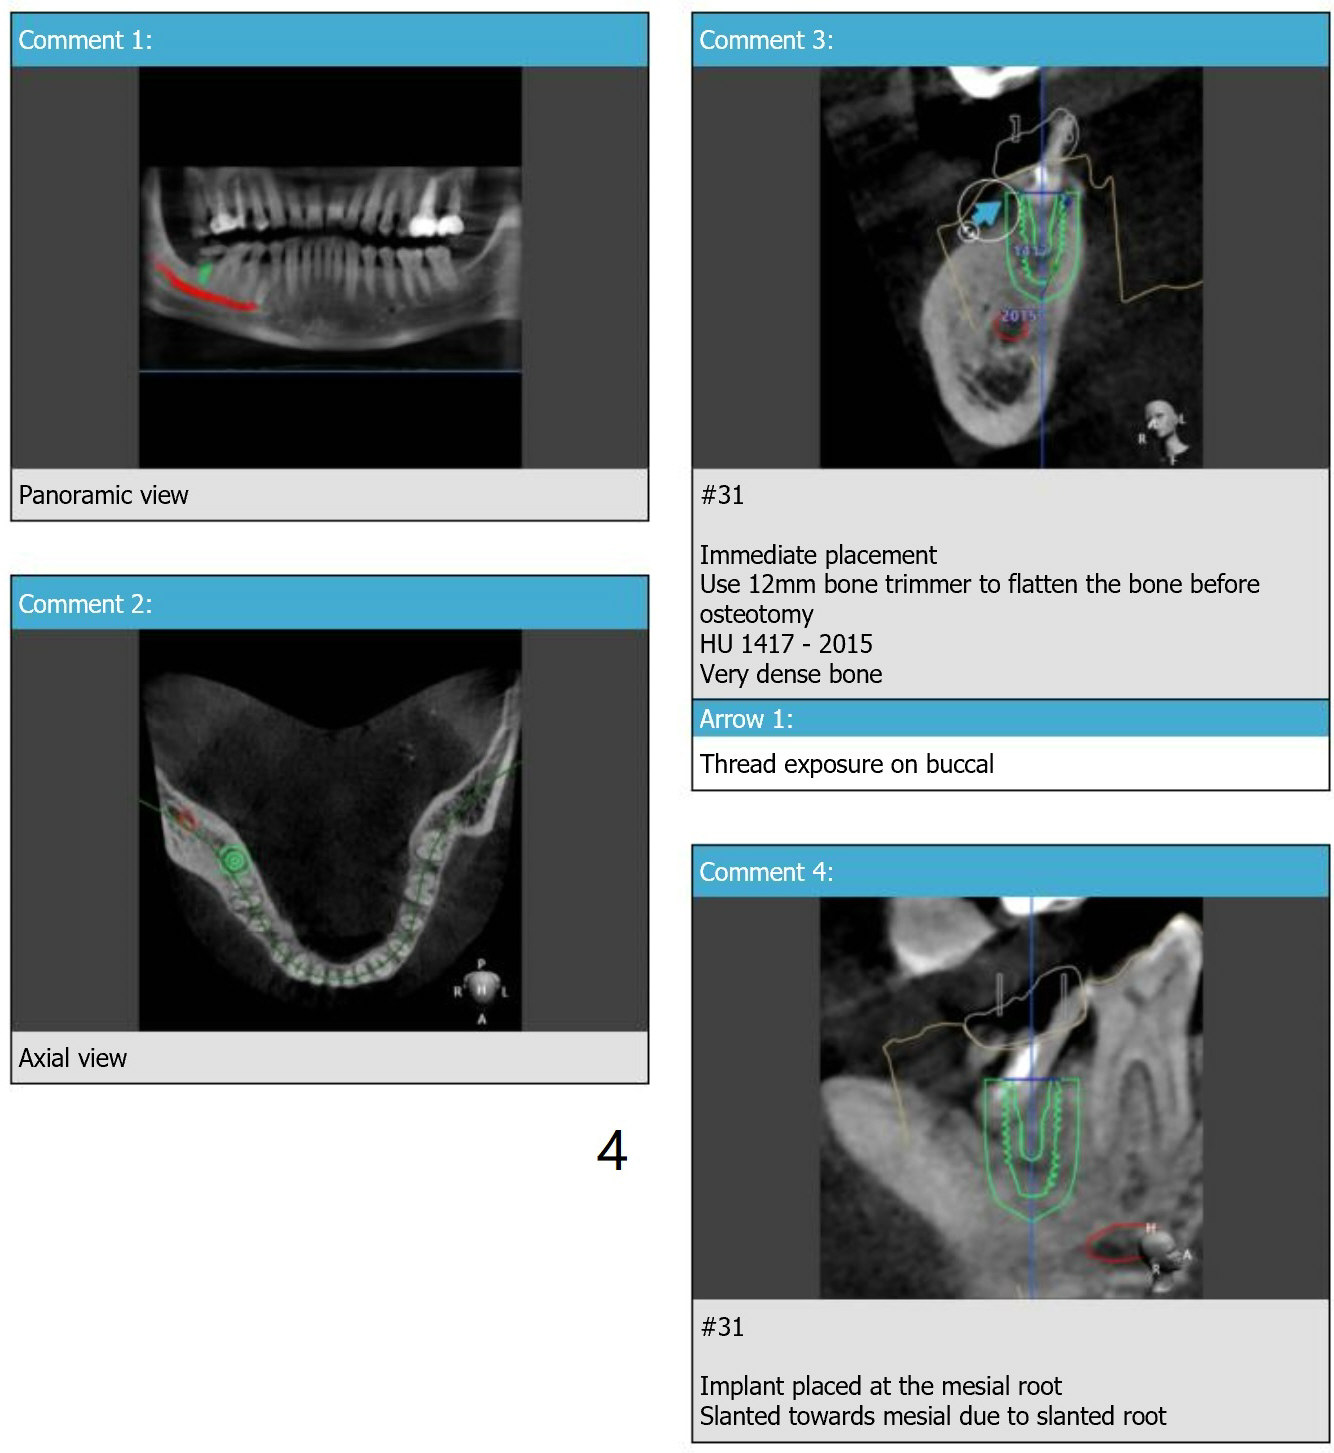

Dense Bone

A 56-year-old man agrees to have immediate implant at #31 (Fig.1-5) 2 year post (re)cementation at #14,15. Osteotomy should be gentle with copious irrigation because of dense bone (Fig.4). After implant osteointegration, a provisional will be fabricated to intrude the supraerupted tooth #2 (Fig.5).